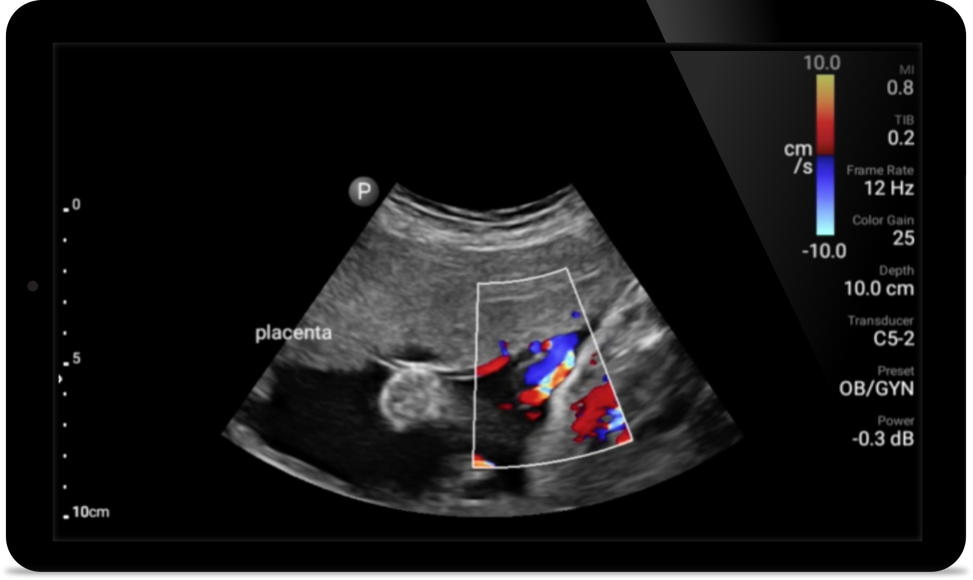

• 5 to 2 MHz extended operating frequency range • 50mm radius of curvature • 2D, color Doppler, M-mode, advanced XRES and multivariate harmonic imaging, SonoCT • High-resolution imaging for deeper applications: abdominal, gall bladder, OB/GYN and lung imaging preset optimizations • Center line marker • USB-C transducer with replaceable cable